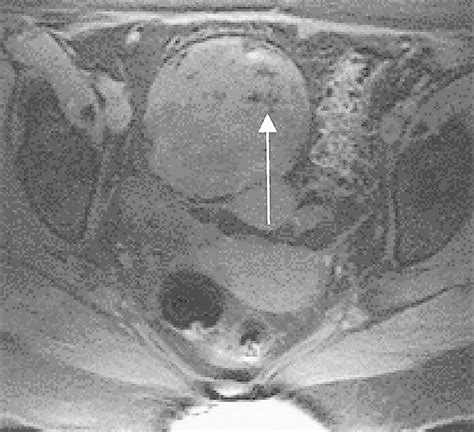

When doctors request scans, they are looking for specific visual identifiers. Imaging techniques such as CT scans, MRIs, and ultrasounds are standard. In these images, a teratoma often appears as a complex mass with both cystic (fluid-filled) and solid components. The presence of fat, calcifications (which look like bone or teeth on an X-ray), and soft tissue elements are hallmark signs that radiologists use to identify the growth.

While looking for Teratoma Cancer Pictures online, patients may see varying representations, but it is important to note that internal clinical imaging (like an MRI) looks significantly different from external surgical photography. Radiology provides the map for surgical intervention, helping surgeons understand the proximity of the tumor to vital organs.